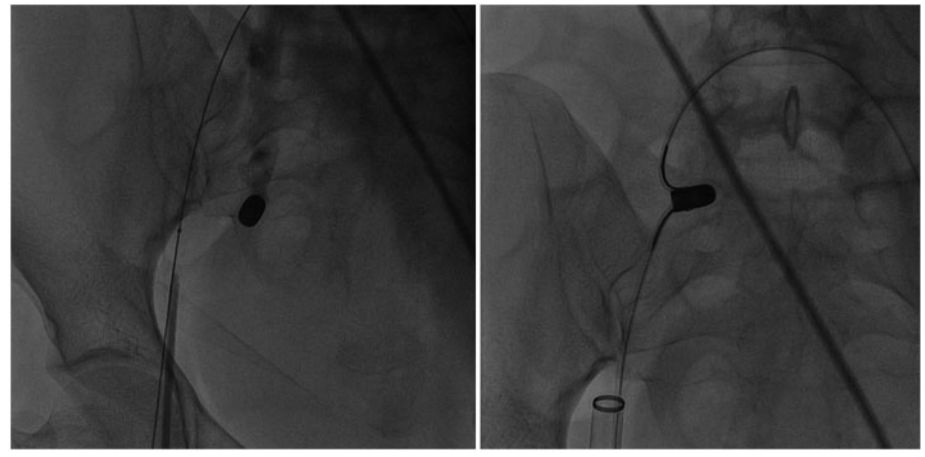

之后,*弹子**滑出向上移动到髂总静脉,并向下移动至右侧髂内静脉,如图4左。为了避免*弹子**滑脱,应在腹股沟*弹子**附近画一8字形缝合线。之后,选择由24-Fr鞘、JR 5-Fr引导管和15 mm的鹅颈管圈套组成的组件通过右侧股静脉,并在右侧股静脉内处理鹅颈管套圈。同时使用两个套圈捕捉*弹子**(图4右侧),并通过24-Fr鞘将*弹子**在右股静脉内安全取出,最终使用8号缝合线缝合静脉。

图4 左:*弹子**在套圈中滑脱,向上移动至右侧髂总静脉,之后又向下移动至右侧髂内静脉;右:两个股静脉套圈均捕获*弹子**